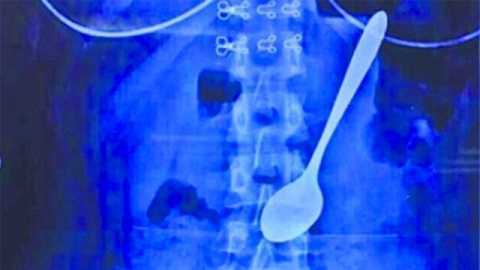

Nữ sinh ăn kem nuốt luôn thìa 14cm vào bụng

Một sinh viên ở Trung Quốc đã nuốt cả chiếc thìa dài 14cm vào bụng khi đang ăn kem.